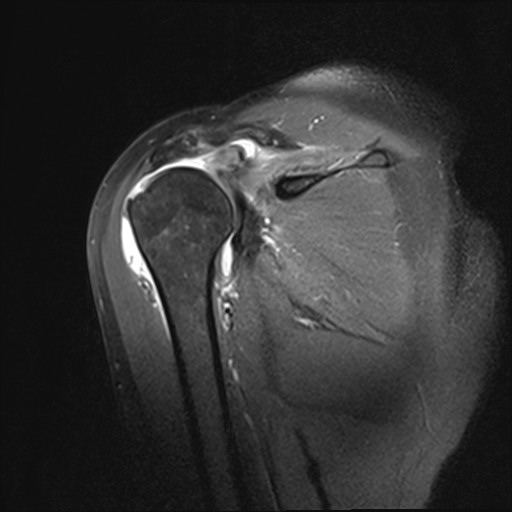

Rotatorenmanschettenriß in der Kernspintomographie

ROTATORENMANSCHETTENMASSENRUPTUR

Rotatorenmanschettemassenruptur: Supraspinatusabriss

Der Patient berichtet, dass er beim Volleyballspiel beim Überkopfaufschlag eine Schultergelenksverrenkung (Luxation) erlitten habe. Er habe bereits zuvor leichte Beschwerden gehabt. In der Kernspintomographie zeigte sich ein Sehnenabriss an der Supraspinatussehne wie auch eine Kapselverletzung am vorderen unteren Gelenk. Arthroskopisches Vorgehen mit Rekonstruktion der Läsionen. Der Patient demonstriert nach 6 Monaten im Januar 2022 eine stabile Schulter im Rahmen der Liegestütze. Eine Wiederaufnahme des Volleyballspielens ist im Weiteren geplant.

62-jährige Patientin mit erheblichen Schmerzen und vollschichtiger Supraspinatussehnenablösung. Die Sehne war sehr weit zurückgezogen, bereits sichtbar auf der präoperativen Kernspintomographie und ließ sich auch intraoperativ nicht so weit mobilisieren. Eine Rekonstruktion war spannungsarm nicht möglich. Es wurde ein mit Flüssigkeit gefüllter Ballon unter dem Schulterdach arthroskopisch gestützt eingeschoben und entfaltet. Dieser Ballon führt neben einer Abstandshaltung zum Schulterdach zu einer Fremdköperreaktion und Membranbildung. Durch die anhaltende Trainingstherapie konnte die Patientin trotz des Defektes eine Rezentrierung des Gelenkes mit sehr guter anhaltender Funktion erzielen.

Infraspinatus und Subscapularis intakt

Supraspinatusdefekt